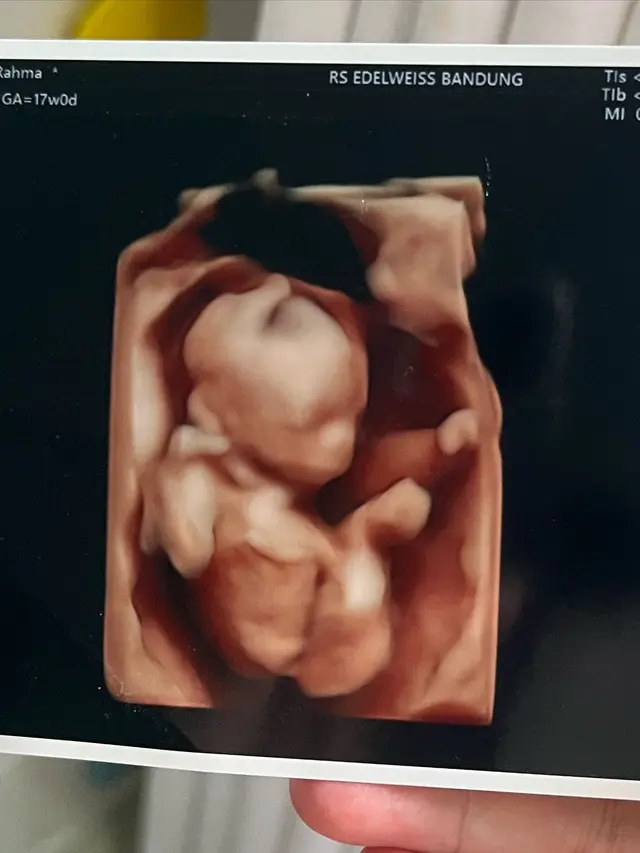

Fimela.com, Jakarta Kabar bahagia datang dari keluarga Anisa Rahma dan Anandito Dwi Sepdiawan. Anisa baru-baru ini membagikan kabar kehamilannya yang kedua, setelah dikaruniai anak kembar pada kehamilan pertama.

"Bismillah twins mau punya adek," kata Anisa Rahma di laman Instagramnya, anisarahma_12.

Dalam unggahannya tersebut, Anisa Rahma dan suaminya terlihat begitu bahagia dan antusias dengan memperlihatkan alat tes kehamilan yang tampak pada tanda positif hamil. Anisa pun membagikan kisahnya kepada khalayak.

Anisa sendiri mengaku bahwa dirinya seperti sedang mimpi karena kehamilan kali ini. Sebagaimana diketahui, Anisa sebelumnya menjalanin program bayi tabung karena ditengarai ada masalah pada alat reproduksinya.

"MasyaAllah masih berasa mimpi klo kali ini aku bisa positif hamil secara alami, karna kehamilan sebelumnya kan lewat program bayi tabung, dengan permasalahan aku yang tersumbatnya kedua saluran tuba falopi," tuturnya.

Menurut medis, karena ada diagnosa mengenai permasalahan pada saluran tuba falopi, maka Anisa disebut akan susah hamil. Hal itu pula yang membuatnya menempuh program bayi tabung bersama suaminya.

"Jadi kalo secara medis sulit untuk bisa hamil alami.. Qodarullah memang kalo Allah berkehendak semua bisa terjadi," ujar Anisa Rahma.